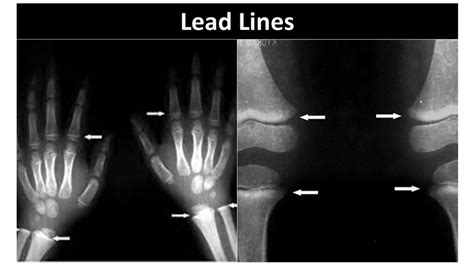

Rose Faulk Blog